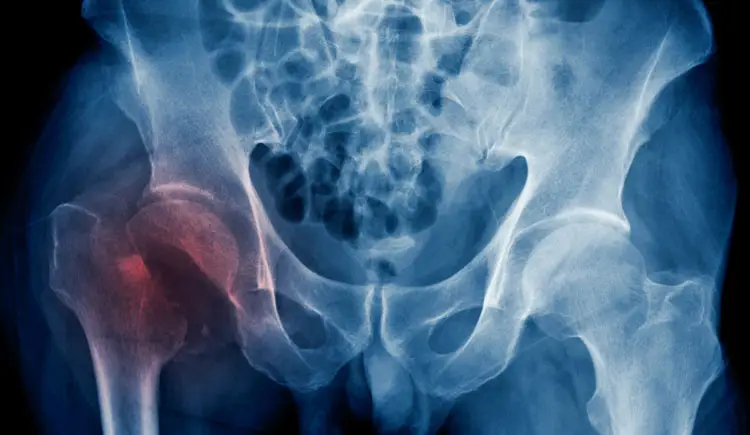

Hip Conditions

We provide treatment for hip problems—helping you move with ease, reduce pain, and return to your everyday activities.

- Hip osteoarthritis

- Hip replacement surgery

- Hip fracture surgery

- Hip impingement

- Hip osteonecrosis

- Snapping hip conditions